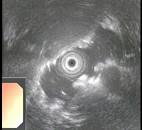

问题 患者,男性50岁,近2个月来出现中上腹隐痛,餐后更甚,伴早饱、厌食,乏力,无发热、黄疸,体重减轻了5Kg,大便隐血阳性,胃镜检查如图,则该患者最可能的诊断是 ( )

选项 A、胃癌 B、食管癌 C、消化性溃疡 D、胃溃疡出血 E、慢性胃炎

答案 A